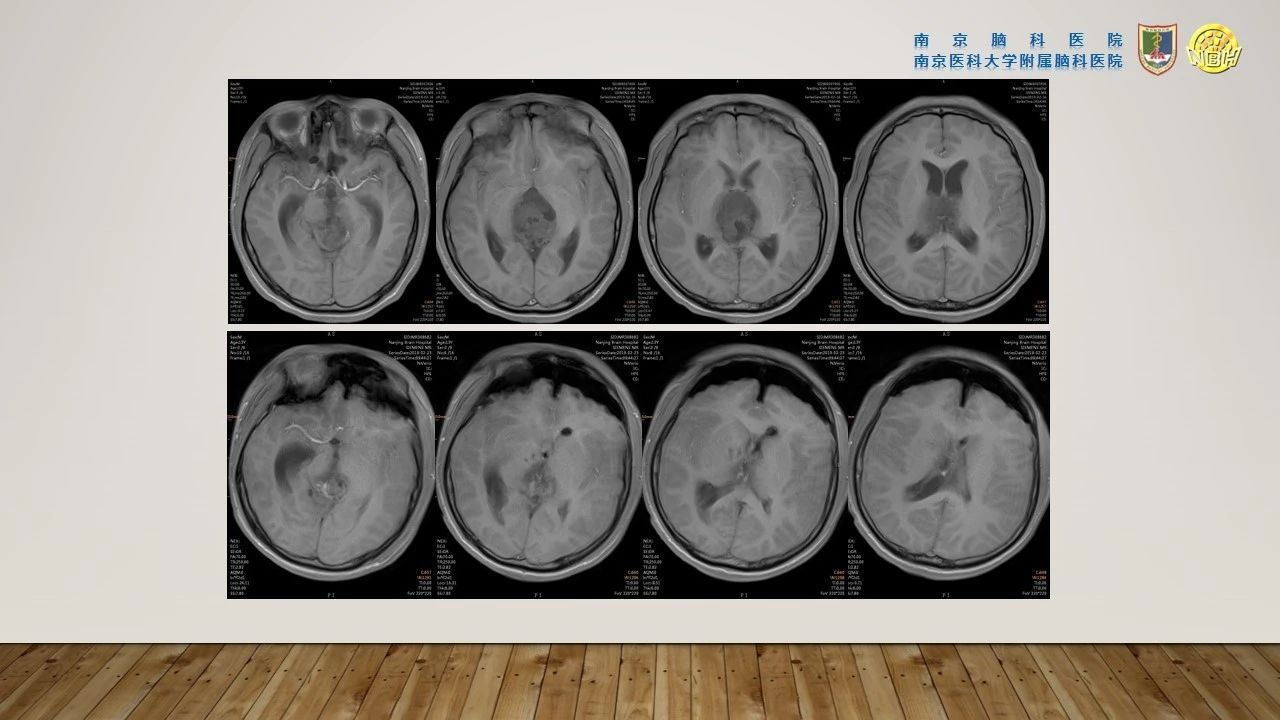

术后状态